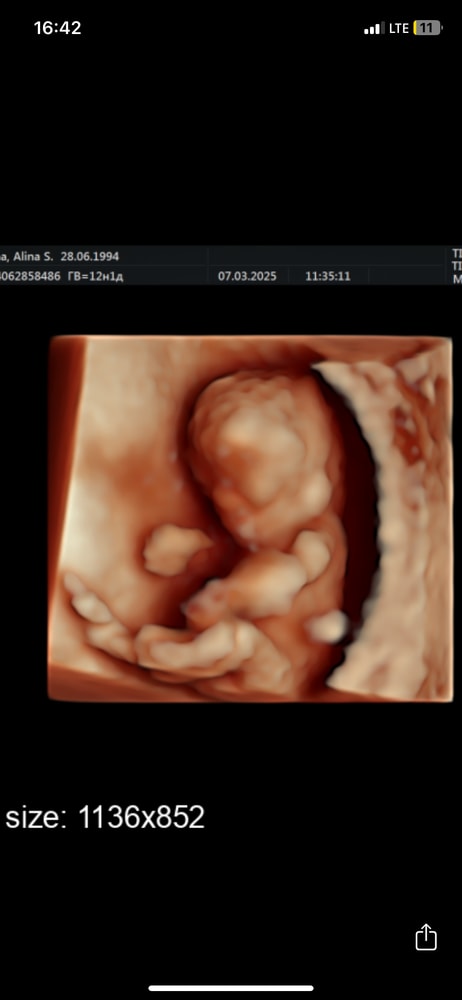

У меня разнополая двойня, поэтому скрининг проводили на том же сроке))) в целом все почти одинаково:) Изображение

Алина, Изображениедоча в 12 недель.

Алина, мне было видно её без бугорка. Вот эта утонченнтсть, Вам не видно? 😅

Анюта Денисова, нееет, у меня круглый бутуз, там утонченности нет😄 она была в 11.4, а через неделю как ветром сдуло Изображение

Алина, 3Д так себе Изображение